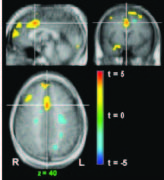

VR has seen interesting applications in areas such as stroke rehabilitation. Stroke patients may experience weakness or paralysis of limbs and must undergo physical rehabilitation to regain control. VR has been proven to be an interactive and enjoyable intervention method to improve upper extremity motor function, however, the neural mechanisms supporting its use has only been recently investigated. Following the development of fMRI compatible VR delivery systems, researchers from Yeungham University and Sungkyunkwan University in Korea and Hampton University in the United States conducted an experimenter-blind randomized study of ten chronic stroke patients that resulted in interesting brain activity pre- and post-VR. Among the movements of brain activity, the study found that cortical activation was reorganized before VR, from ipsilateral activation, and after VR, to contralateral activation (Figure 2). Overall, it was shown that VR contributed to positive changes in neural organization and was one of the pioneering studies that explored the effectiveness of VR in neurorehabilitations.

Figure 2: MRI scans of live patients. A: diagnostic MRI images, B: before VR, showing ipsilateral activations, C: after VR, showing decreased ipsilateral activations